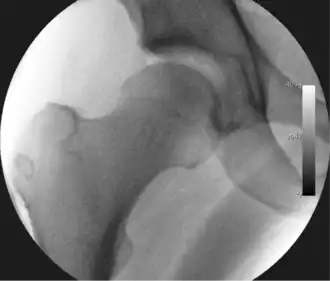

![]() Intraoperative fluoroscopic image during an arthroscopic resection of a cam lesion of the femur. The upper instrument is the arthroscope (viewing device), while the lower is the high-speed burr used for reshaping the bone. |